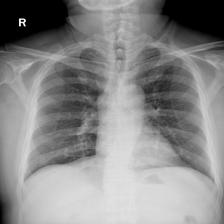

To pre-train a high-performance X-ray foundation model, the first thing we need to do is the collection of large-scale X-ray images. Therefore, a large-scale and high-resolution dataset that contains X-ray medical images is collected for the pre-training. Some representative samples are visualized in Fig. 3.